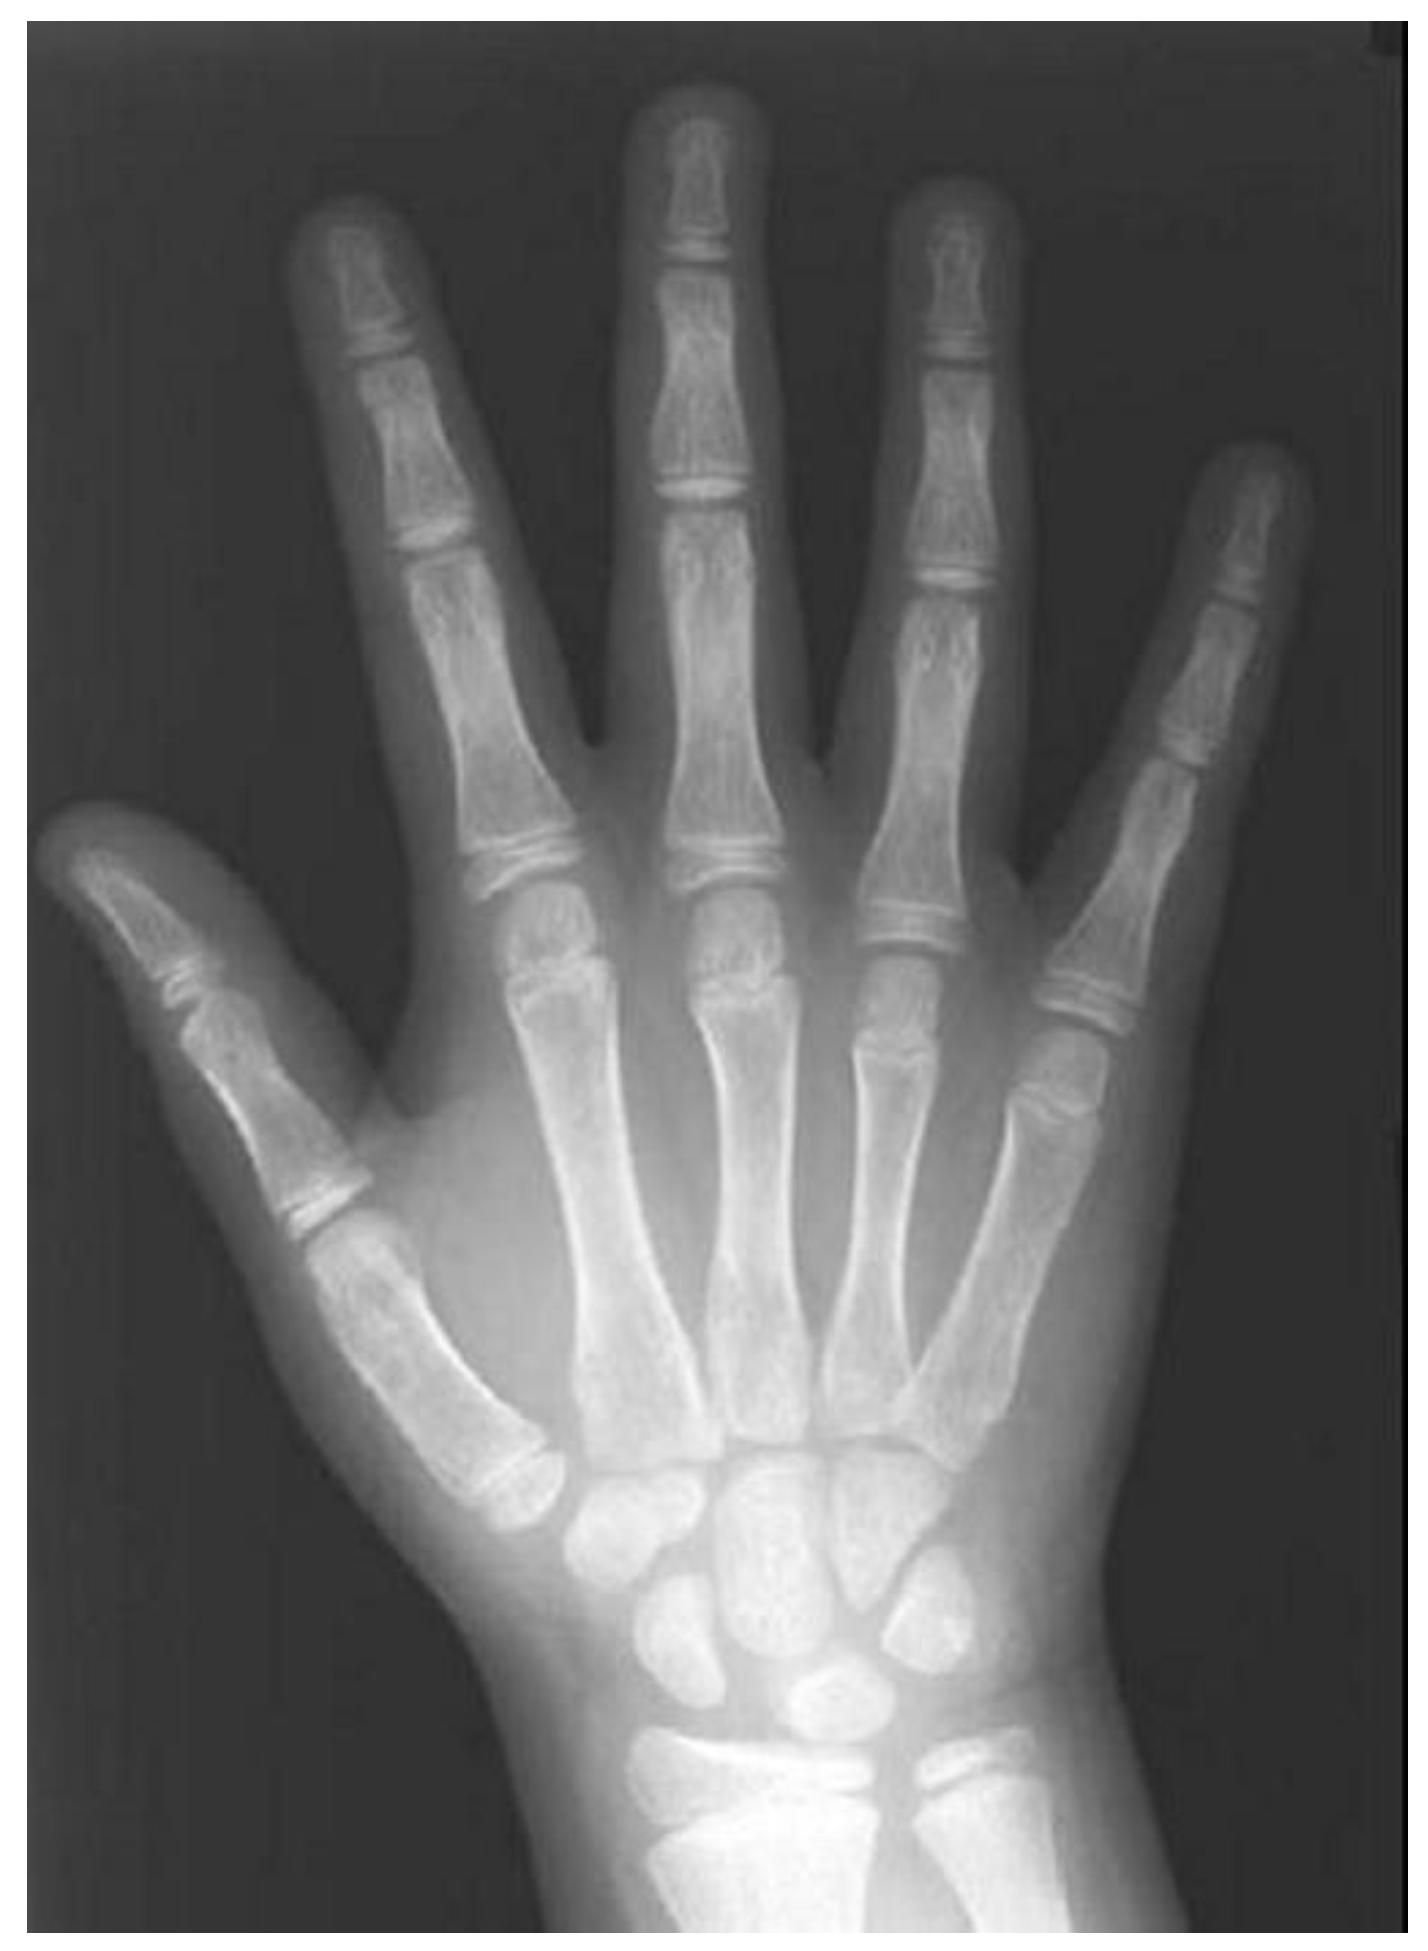

3.3.3. Hand–Wrist Radiograph